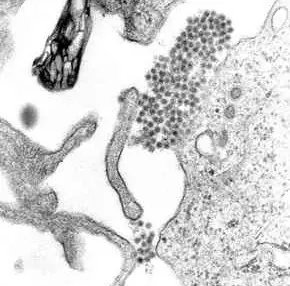

Ces trois arbovirus (1) aux symptômes proches sont véhiculés par le moustique Aedes Aegypti, qui prospère dans les petites retenues d'eau des pots de fleurs, des pneus, des gouttières ou de n'importe quel récipient.

(1) Les arbovirus sont des virus ayant pour vecteur les arthropodes suceurs de sang (moustiques, tiques...). Les maladies associées sont nommées arboviroses.